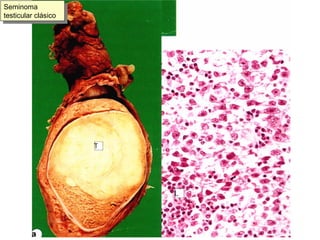

Seminoma testicular clásico

Seminoma (testículo) o Disgerminoma (ovario) Fondo “tigroide”,  células con  citoplasmas desdibujados y grandes núcleos,  junto a linfocitos

Seminoma o disgerminoma, grandes núcleos con nucleolos evidentes de tamaño medio. Mitosis.